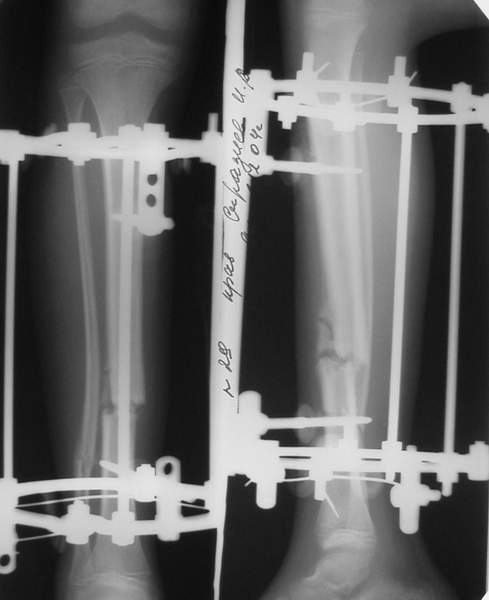

В аттачтах №№ 1 и 2 - примеры, когда 2 кольца не позволили послеоперационно

исправить смещение фрагментов большеберцовой (по ширине и вальгусное).

А казалось бы (#2) - поиграй на штангах и все влетит.

Оперировал не я

:-)

1

1a